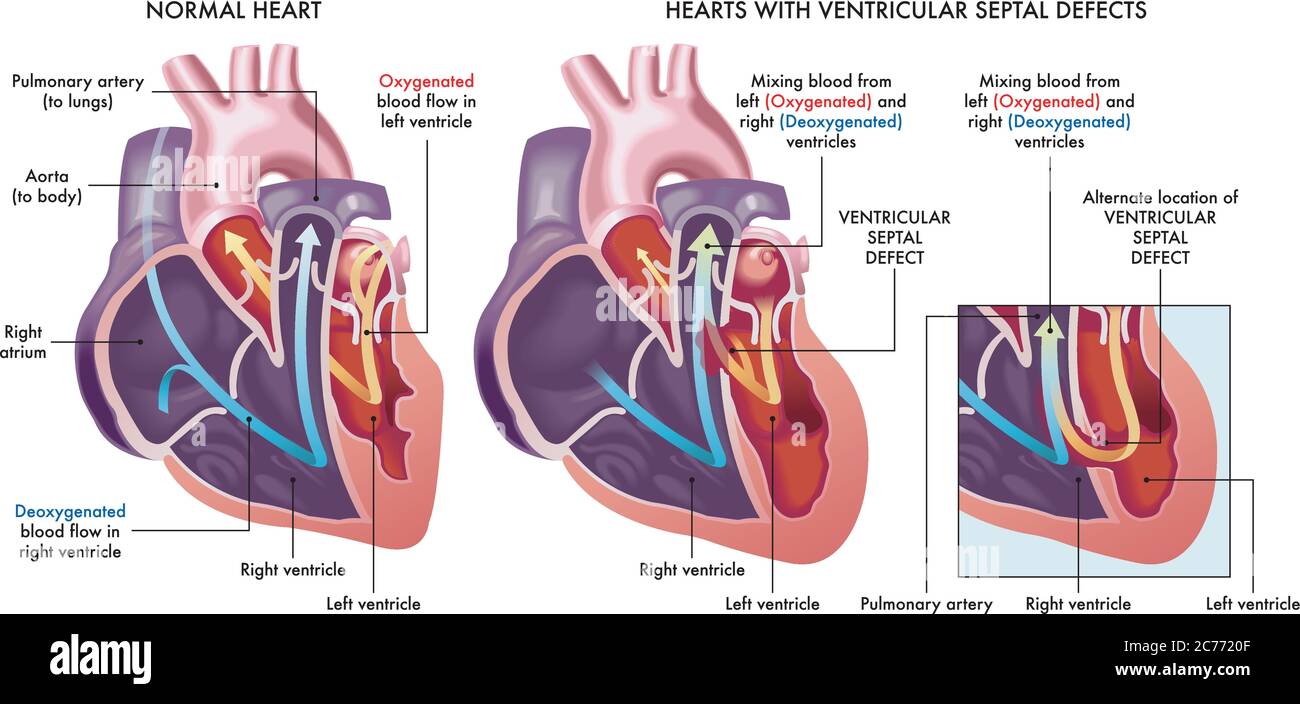

Medical illustration that compares a normal heart with hearts afflicted by ventricular septal defects, an abnormal opening (hole) in the heart, with a Stock Vectorhttps://www.alamy.com/image-license-details/?v=1https://www.alamy.com/medical-illustration-that-compares-a-normal-heart-with-hearts-afflicted-by-ventricular-septal-defects-an-abnormal-opening-hole-in-the-heart-with-a-image365875567.html

Medical illustration that compares a normal heart with hearts afflicted by ventricular septal defects, an abnormal opening (hole) in the heart, with a Stock Vectorhttps://www.alamy.com/image-license-details/?v=1https://www.alamy.com/medical-illustration-that-compares-a-normal-heart-with-hearts-afflicted-by-ventricular-septal-defects-an-abnormal-opening-hole-in-the-heart-with-a-image365875567.htmlRF2C7720F–Medical illustration that compares a normal heart with hearts afflicted by ventricular septal defects, an abnormal opening (hole) in the heart, with a